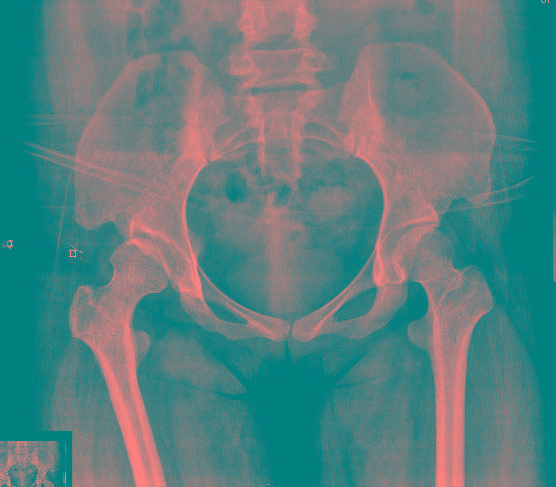

女.29岁.先天髋关节脱位.腰椎后部向外膨出.外院诊断骨肉瘤.我院诊断夏科氏关节病。

女.29岁.先天髋关节脱位.腰椎后部向外膨出.外院诊断骨肉瘤.我院诊断夏科氏关节病请大家讨论!

该患者有脊柱裂和右侧髋臼发育不良,踝关节改变符合神经性骨关节病,必要时结合临床排除结核.

2、右侧髋臼发育不良伴半脱位;

1、脊柱裂;    2、右侧髋臼发育不良伴半脱位;     3、双踝关节夏科氏关节病。

支持:1、隐性脊柱裂;

3、双踝关节改变符合神经营养性关节病(夏科关节);

4、双侧髂骨致密性骨炎。

但是腰椎和骨盆表现像是骨骺发育不良

1、脊柱裂;伴脊髓脊膜膨出?建议mri检查,

1、脊柱裂;

3、双踝关节夏科氏关节病;

4、双侧髂骨致密性骨炎.